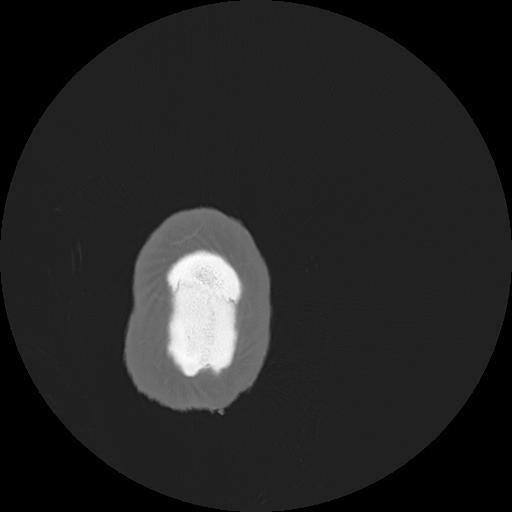

7 HUESO,,Vol,0.5,HUESO,,